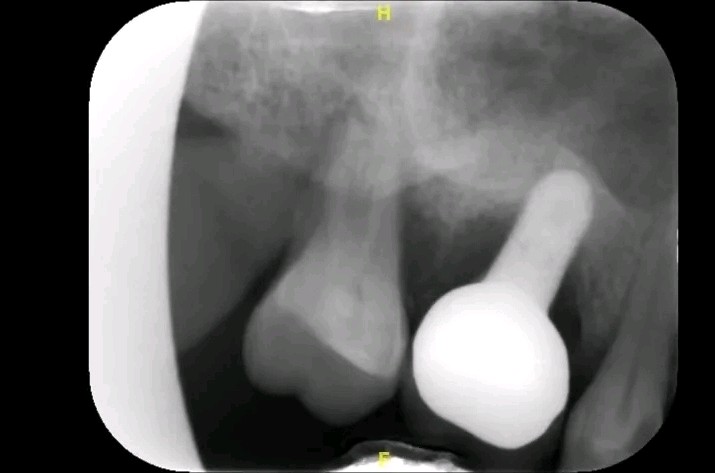

术前 拍摄x 线片发现种植体颈部周围出现明显牙槽骨破坏。

诊断:16(第一磨牙)种植体周围炎